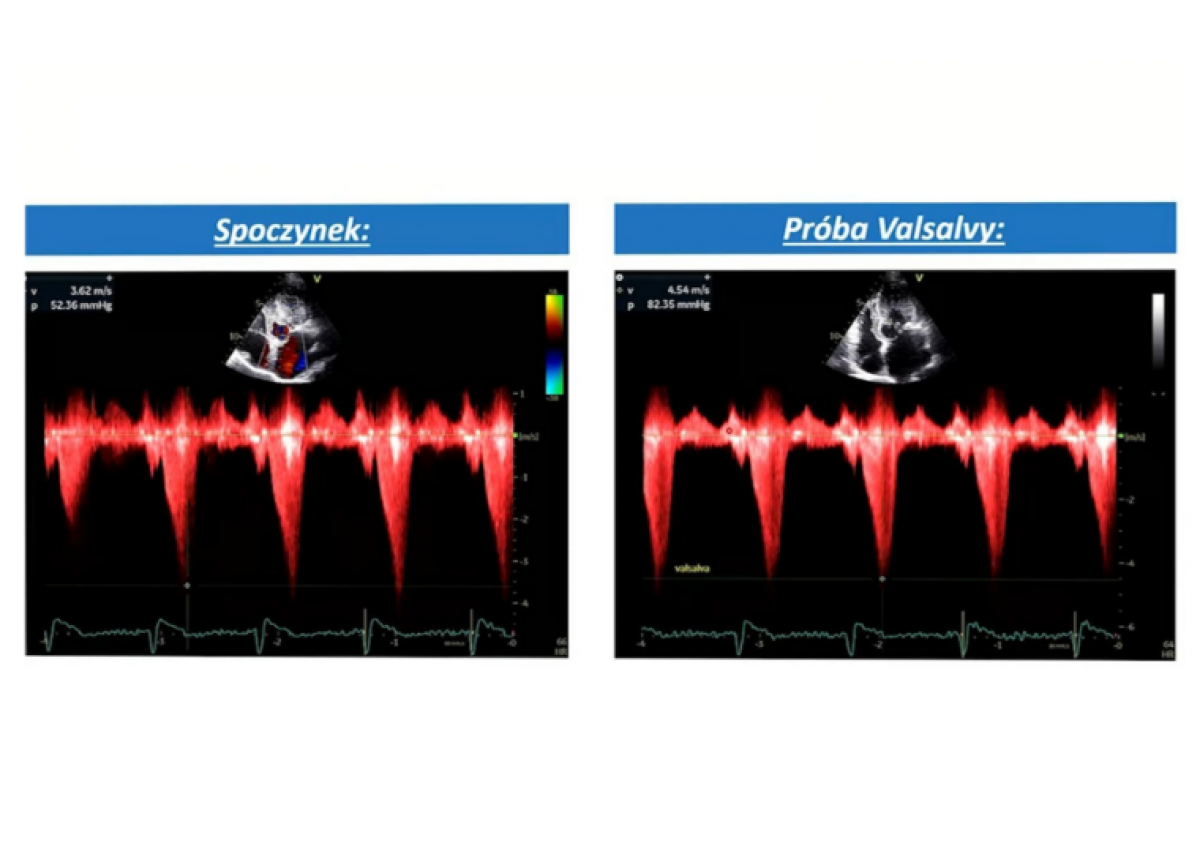

Kardiomiopatia przerostowa z zawężaniem drogi odpływu lewej komory

Echokardiografia przezklatkowa

Diagnostyka kardiomiopatii przerostowej